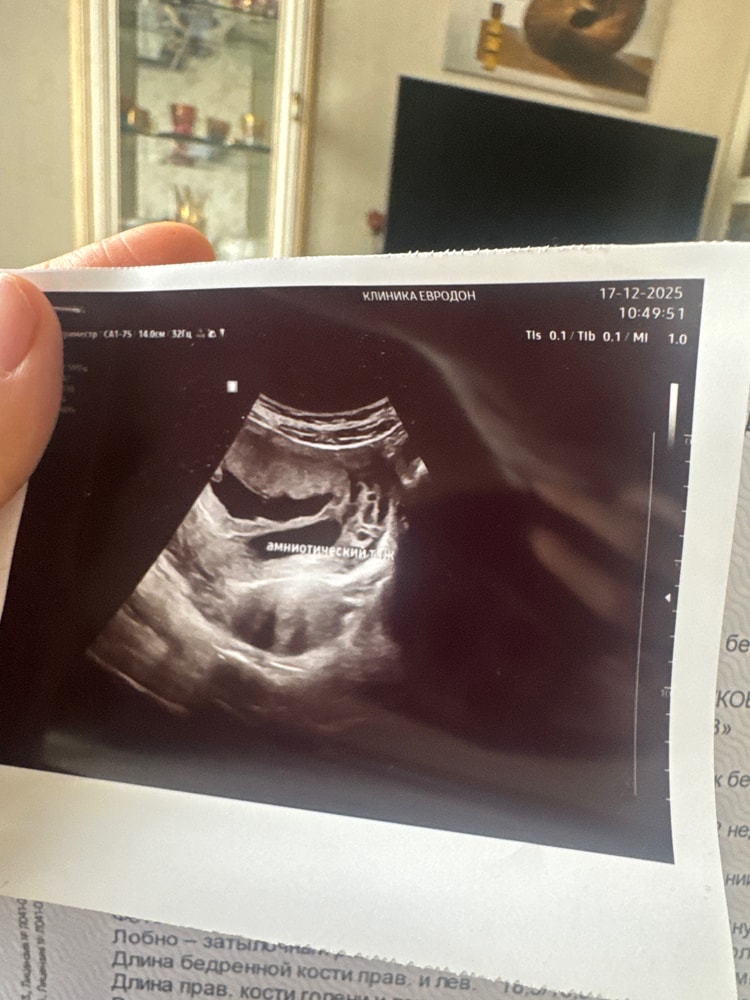

Dinara в Зачатие 2 часа Амниотический тяж УЗИ Девочки, вот фото моего тяжа, 15 недель 1 день, мне ничего не сказали , только наблюдать, у кого-то был такой? Я даже не понимаю где он расположен и опасен ли. Напишите если в чем-то таком разбираетесь или у вас было 🫂 Посмотрите еще 20 записей на эту тему Отменить Ответить Анвуляторный цикл Чаты Беременных Выберите чат: Январята-2026 Февралята-2026 Мартята-2026 Апрелята-2026 Майчата-2026 Июнята-2026 Июлята-2026 Августята-2026